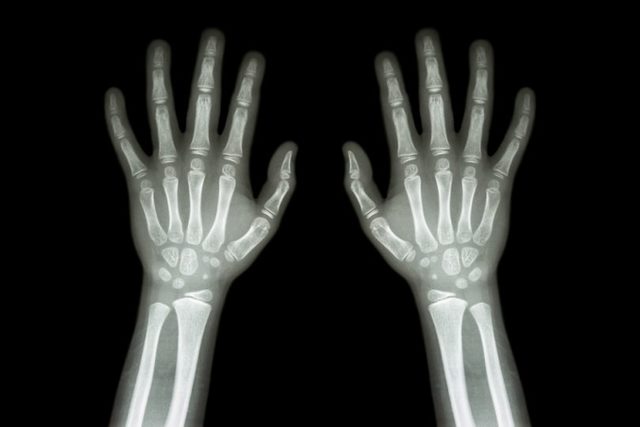

Dentro de la disciplina de la Anatomía descriptiva podríamos encuadrar lo que conocemos como Anatomía Radiológica, nacida en virtud al desarrollo de las potentes técnicas de imagen del cuerpo humano. El origen de estas técnicas, que permitieron el inicio del estudio de la Anatomía en el individuo vivo, surgió en 1896 cuando se realizó la primera radiografía de la mano humana, tras el descubrimiento de los rayos X en 1895 por el premio Nobel de física alemán